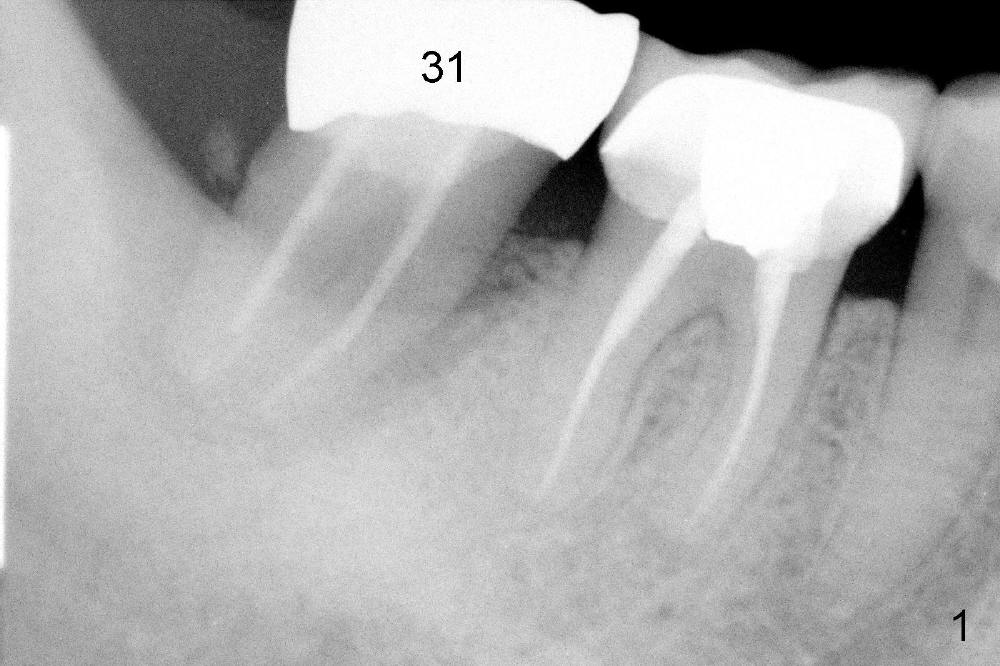

A 62-year-old lady has an advanced endo-perio disease associated with the tooth #31 (Fig.1). IAN is not distinct in the preop PA. IAN is assumed far away from implant area. The implant is planned to be placed along the long axis of the tooth for the best restorative result (Fig.2). The tissue-level implant is placed ~ 3 mm above the distal crest so that implant threads may be less likely exposed postop. Is it a good treatment plan?